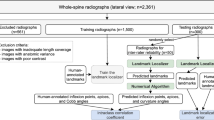

Analyzing spinal curvatures manually is time-consuming and tedious for clinicians, and intra-observer and inter-observer variability can affect manual measurements. In this study, we developed and evaluated the performance of an automated deep learning–based computer-aided diagnosis (CAD) tool for measuring the sagittal alignment of the spine from X-ray images. The CAD system proposed here performs two functions: deep learning–based lateral spine segmentation and automatic analysis of thoracic kyphosis and lumbar lordosis angles. We utilized 322 datasets with data augmentation for learning and fivefold cross-validation. The segmentation model was based on U-Net, which has multiple applications in medical image processing. Here, we utilized parameter equations and trigonometric functions to design spinal angle measurement algorithms. The kyphosis (T4–T12) and lordosis angle (L1–S1, L1–L5) were automatically measured to help diagnose kyphosis and lordosis. The segmentation model had precision, sensitivity, and dice similarity coefficient values of 90.53 ± 4.61%, 89.53 ± 1.8%, and 90.22 ± 0.62%, respectively. The performance of the CAD algorithm was also verified with the Pearson correlation, Bland–Altman, and intra-class correlation coefficient (ICC) analysis. The proposed angle measurement algorithm exhibited high similarity and reliability during verification. Therefore, CAD can help clinicians in reaching a diagnosis by analyzing the sagittal spinal curvatures while reducing observer-based variability and the required time or effort.